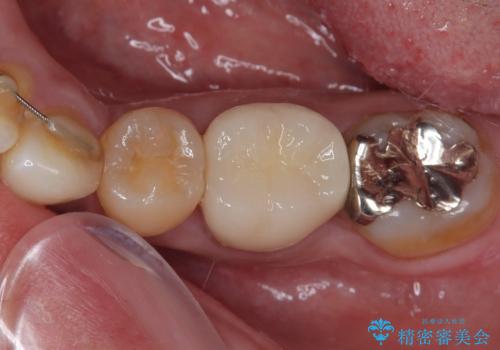

セラミック治療の注意事項(リスク・副作用など)

- 天然歯を削ります

- 硬い素材は天然歯を傷つけてしまう場合があります

- かみ合わせや歯ぎしりが強すぎる方はセラミックが割れてしまう可能性があります

- 自費診療(保険適用外治療)となります